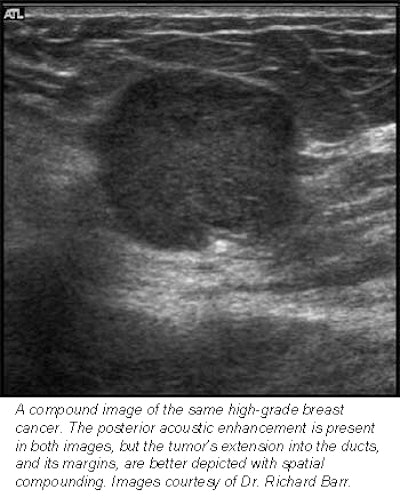

Hoping to ascertain the clinical worth of this new technology, Barr evaluated 100 breast lesions with both conventional and compound imaging. All 200 images were then read both randomly and side-by-side, in which both images of the same lesion were compared.

In the random analysis, viewers rated 91% of the compound images excellent in terms of margin definition, as well as near-field, lesion, and anatomic details. In the comparative analysis, compound ultrasound rated similar to conventional ultrasound in 82% of patients in depicting near-field detail and small structures such as ducts. And it rated better than conventional ultrasound in all patients for margin and lesion definition, as well as reduced speckle.

![]() |

"Now, we can see if a tumor has advanced into a duct," Barr said. "Sometimes, these things are very small, and only with compound imaging can you tell if something is clutter noise or if it’s real."

Barr did find, however, that compound imaging lagged behind conventional ultrasound in shadowing and through-transmission. As he explained, shadowing occurs when sound waves hit a dense mass, such as a calcification. In these cases, the sound waves don’t penetrate and instead bounce back, leaving a black, shadowy area on the scan. This mark appears crisp on a conventional scan, but is unfortunately diluted in a compound image, he said.

Likewise, through-transmission occurs in less dense masses such as cysts. Sound waves easily pass through these liquid-filled lesions, resulting in a cyst-shaped bright spot on the scan. Again, these areas appear less crisp on a compound image.